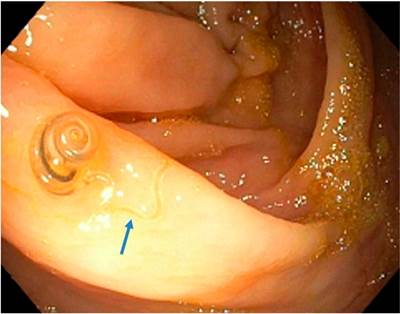

Después de leer el artículo de Pizza y colaboradores 1 sobre el diagnóstico endoscópico de la uncinariasis, considero importante mencionar algunos aspectos relacionados con dicho proceso diagnóstico, ejercido en un paciente con anemia. Este paciente fue llevado a estudios endoscópicos y se le identificó un parásito móvil en el duodeno, así como múltiples vermes en el colon ascendente y en el ciego. Se asumió entonces que los hallazgos presentes en la esofagogastroduodenoscopia y en la colonoscopia eran compatibles con la uncinariasis.

Sin embargo, los helmintos pertenecientes a los géneros Necator americanus y Ancylostoma duodenale se alojan en las porciones superiores del intestino delgado, mientras que los del género Trichuris trichiura residen dentro del ciego y el colon ascendente 2. En el caso descrito por este artículo, debe considerarse que los agentes etiológicos identificados, tanto en la endoscopia como en la colonoscopia, son de diferente especie, si se tienen presentes los sitios de hábitat usual de dichos gérmenes, así como los aspectos macroscópicos claramente evidenciados en las dos fotografías anexas.

En ellas se observa un gusano con un extremo enrollado en el ciego, que semeja las características macroscópicas del T. trichiura macho 2,3) y con un aspecto distinto al verme detectado en la endoscopia alta. Del mismo modo, el T. trichiura puede configurar particularidades clínicas semejantes a la infección por uncinarias, como anemia severa, e incluso es posible que se presente un cuadro de disentería por T. trichiura3,4.

Una de ellas es la extracción del verme con la pinza de biopsia, en caso de identificarse el agente durante los estudios endoscópicos 7. Este procedimiento no solo tiene una finalidad diagnóstica, sino que también es terapéutico, dado que en ocasiones el T. trichiura se encuentra incrustado en la mucosa y no puede ser expulsado luego del tratamiento antihelmíntico 8,9.